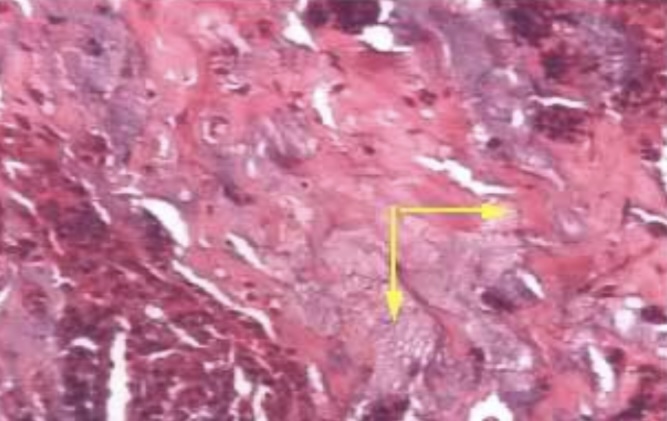

Caseation necrosis